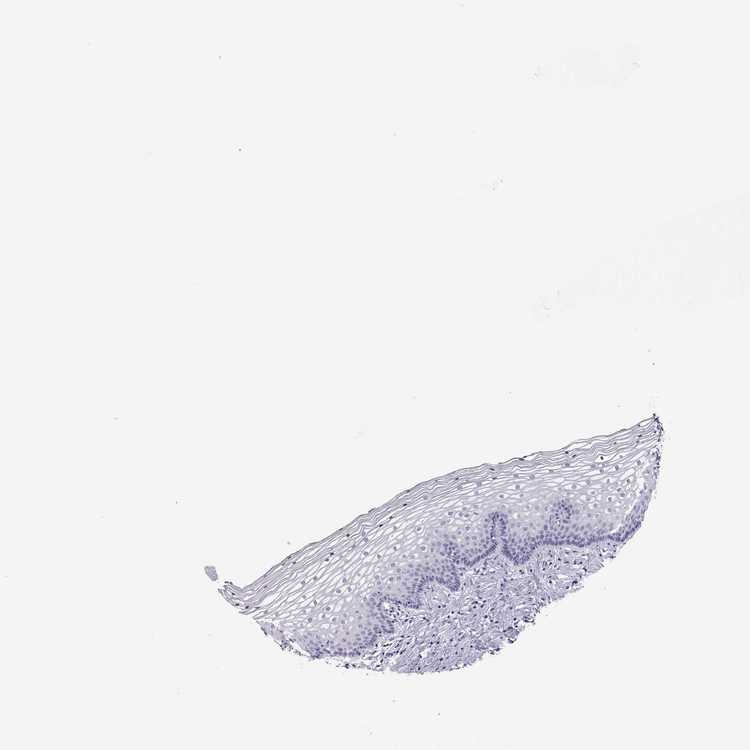

TISSUE PRIMARY DATA VAGINA Show tissue menu

VAGINA - Antibody stainingi

Antibody staining in the annotated cell types in the current human tissue is reported as not detected, low, medium, or high, based on conventional immunohistochemistry profiling in selected tissues. This score is based on the combination of the staining intensity and fraction of stained cells.

Each image is clickable and will lead to virtual microscopy that enables deeper exploration of all samples and also displays staining intensity scores, fraction scores and subcellular localization as well as patient and tissue information for each sample.

Antibody HPA074453

Squamous epithelial cells Not detected